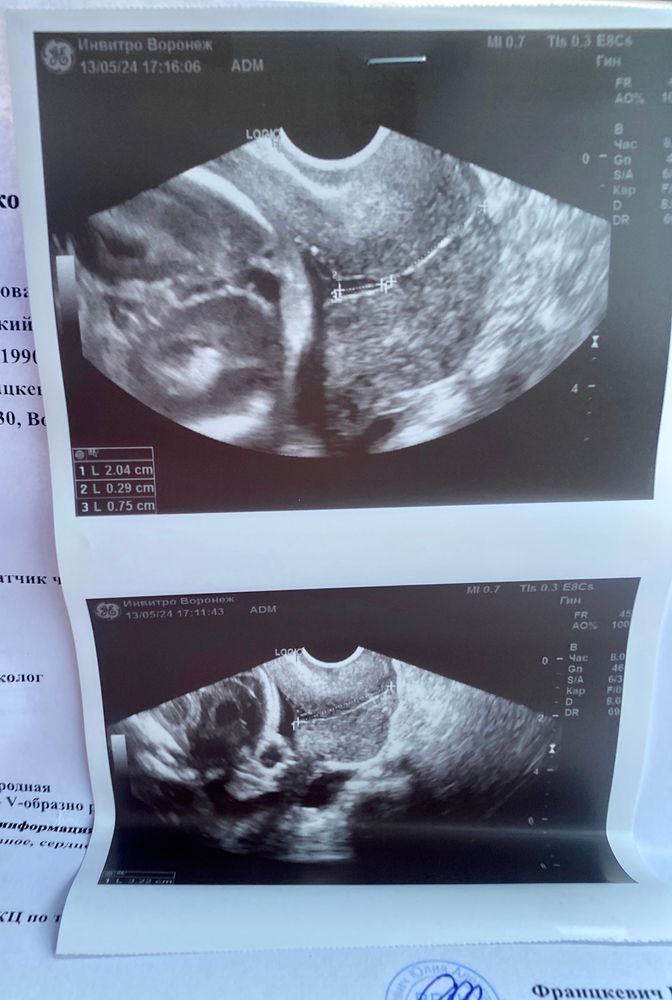

Надо бы ещё её плотность пощупать. У меня была рыхлая шейка и сомкнутая часть 19 мм, воронка 6 мм. Зашили. В плотных шейках воронок нет, они просто то короче становятся, то удлинятся - с такой можно доносить.

14.05.2024

Елена, да, сказали рыхлая(( как вы перенесли? Не было потом проблем со швами?